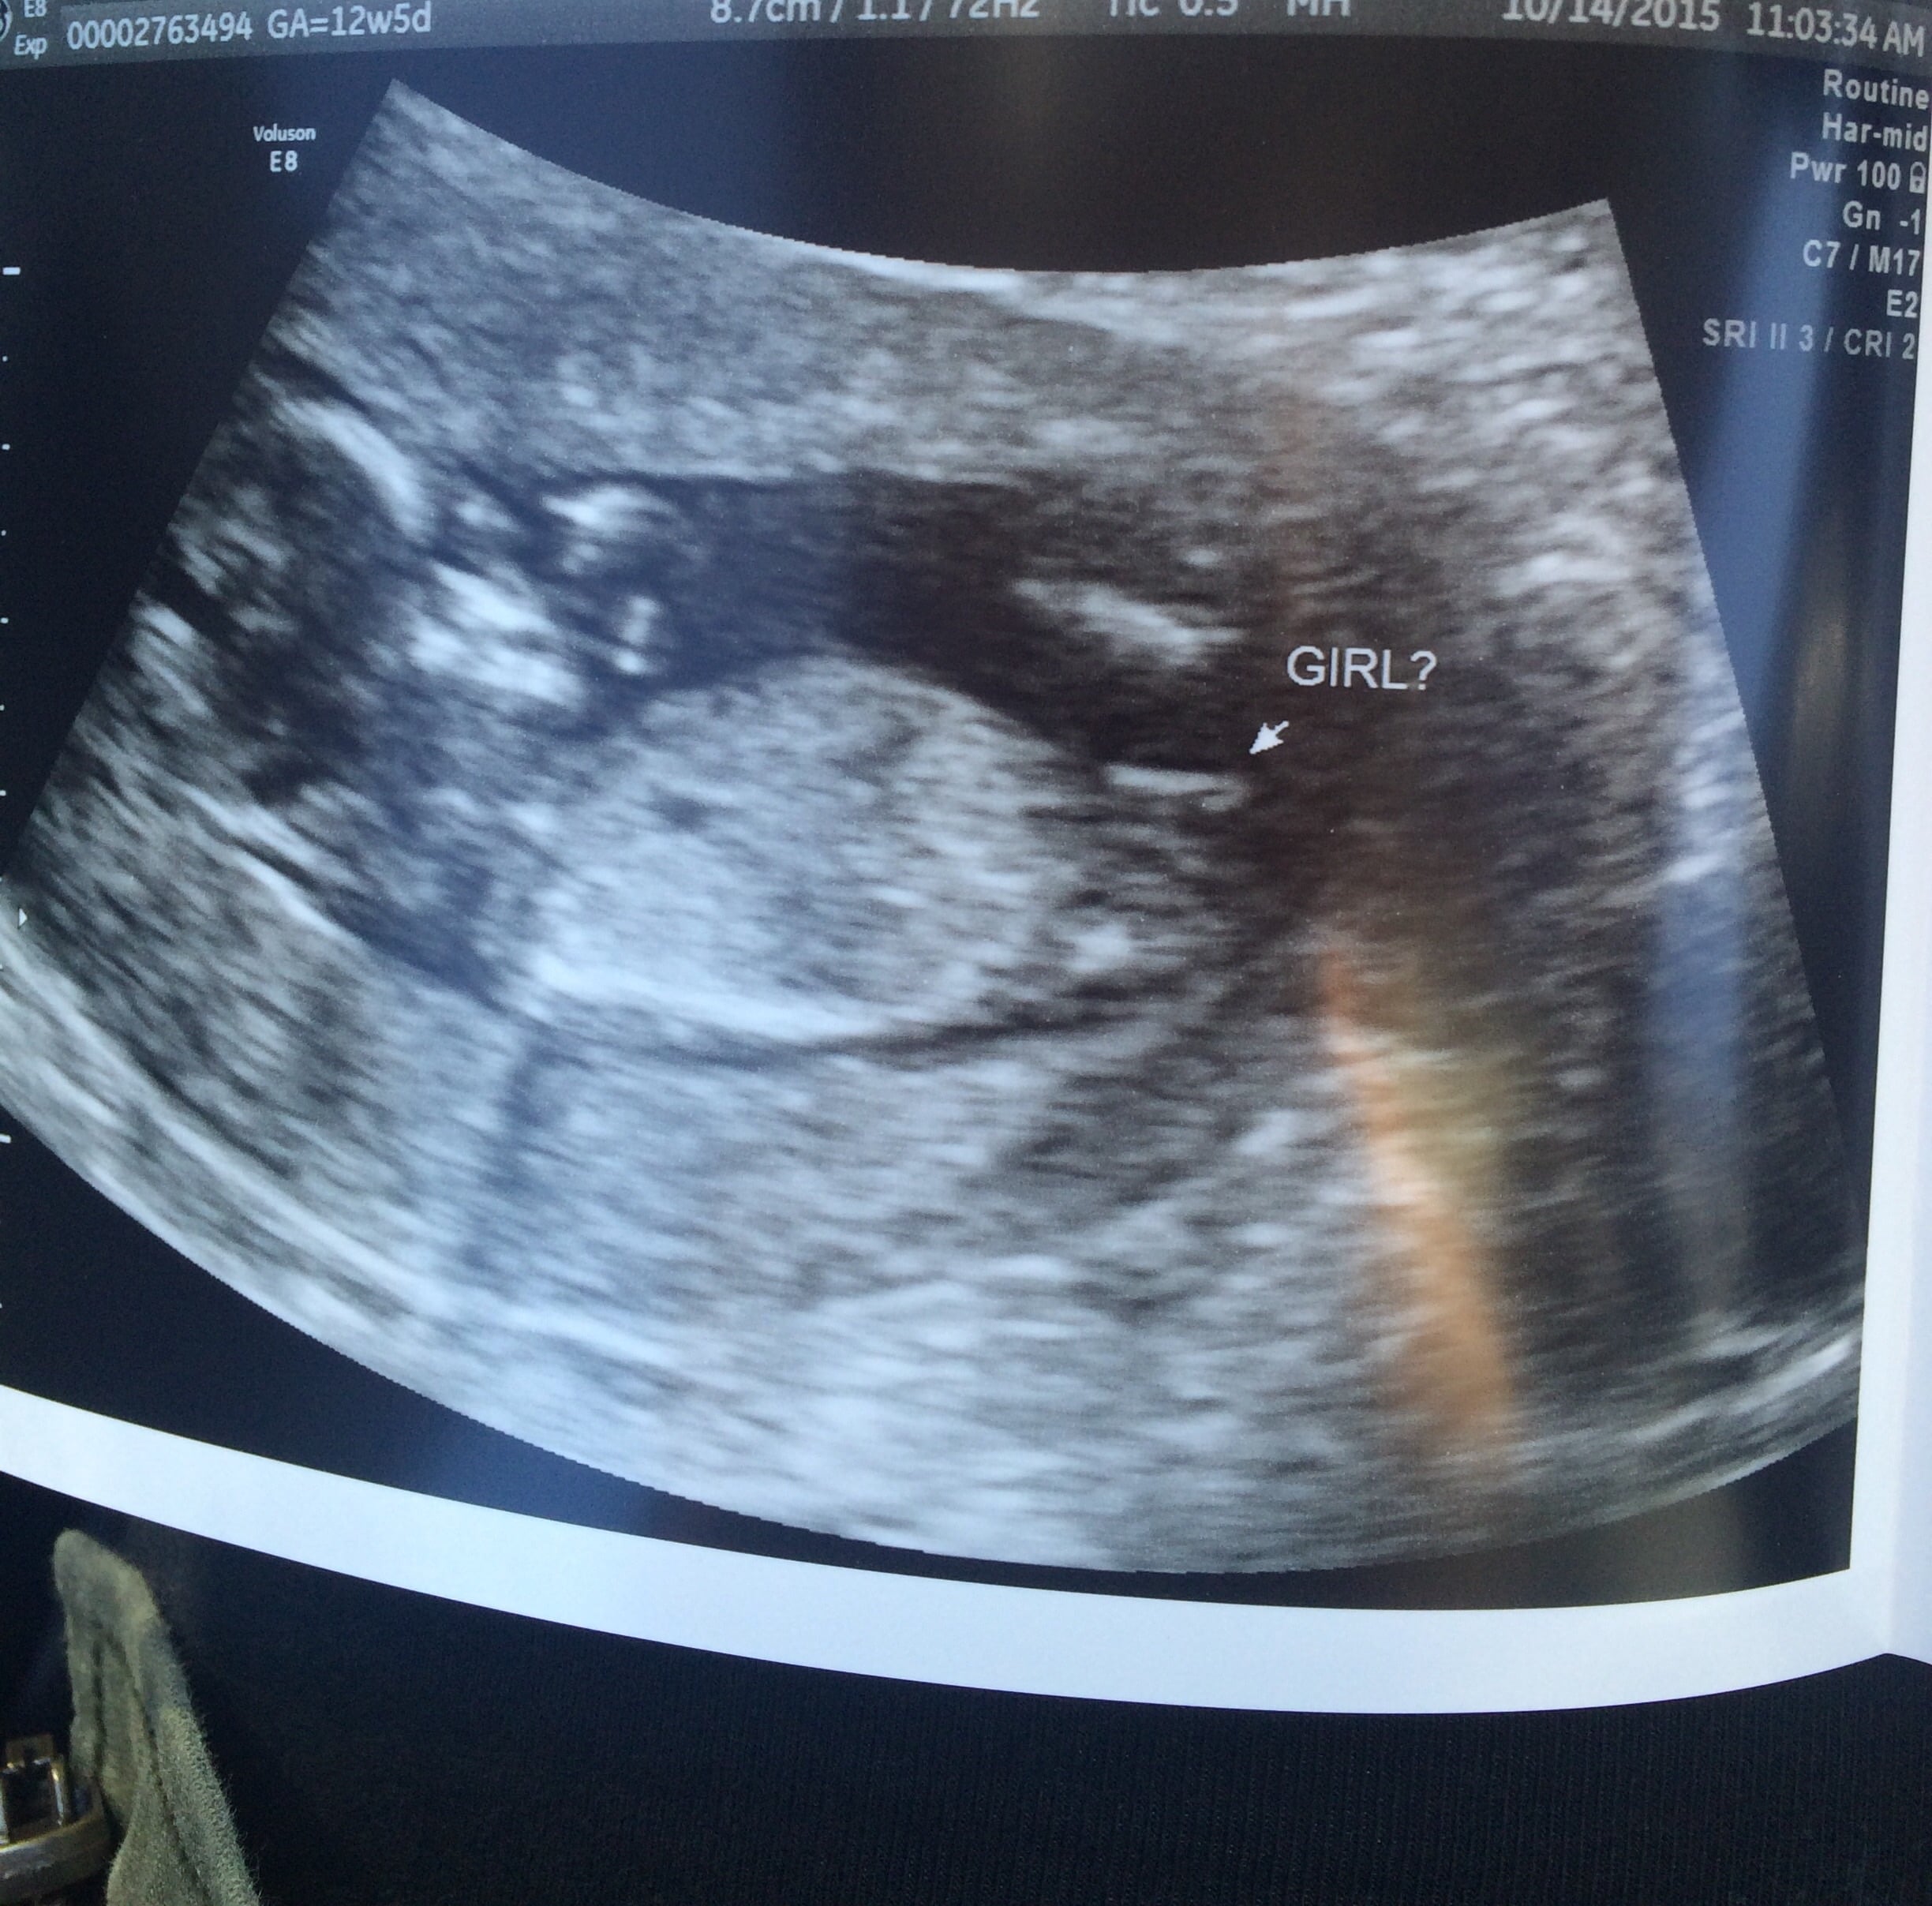

The sonographer said 80% girl what do you think

• Based on angle of the dangle looks like a girl. If you get a good shot at 14 weeks on a decent machine you can tell for sure.